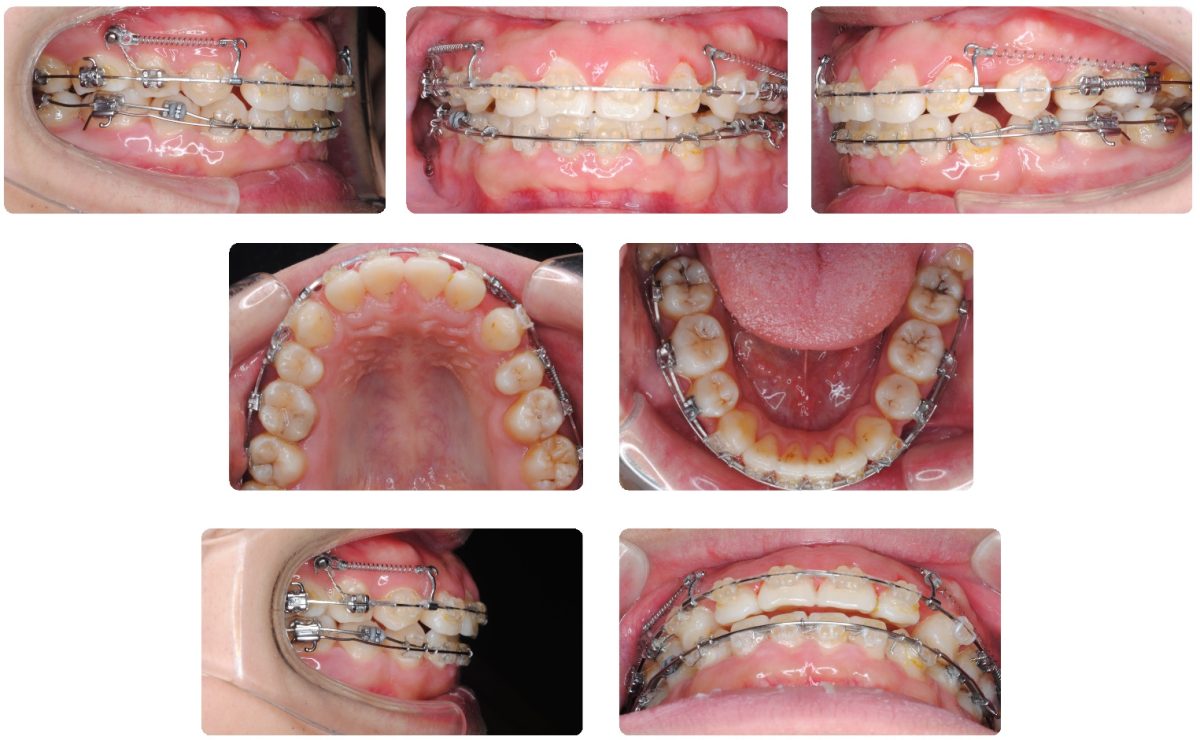

今回紹介する症例は口元が出ていて口が閉じにくいことで来院されました。上顎小臼歯抜歯による治療を選択しました。

上下顎ともに叢生(歯並びの乱れ)がほとんどないため、抜歯スペースを最大限利用して口元を下げていく予定です

治療半ばから治療効率を上げるために上顎右側にアンカースクリューを埋入しました。

動的治療期間は2年6カ月でした。

治療後は口元がかなり下がったため口が楽に閉じれるようになったととても喜ばれました。

今回紹介する症例は口元が出ていて口が閉じにくいことで来院されました。上顎小臼歯抜歯による治療を選択しました。

上下顎ともに叢生(歯並びの乱れ)がほとんどないため、抜歯スペースを最大限利用して口元を下げていく予定です

治療半ばから治療効率を上げるために上顎右側にアンカースクリューを埋入しました。

動的治療期間は2年6カ月でした。

治療後は口元がかなり下がったため口が楽に閉じれるようになったととても喜ばれました。